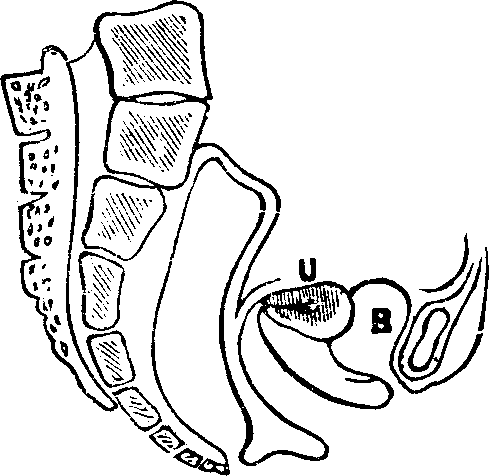

Fig. 15. A representation of the pelvic bones. e. The

lumbo-sacral joint. 2. The sacrum. 3. Coccyx. 1, 1. The

innominata. 4,4. Acetabula.

The Pelvis is an open bony structure, consisting of the Os Innominata, one on either side, and the Sacrum and Coccyx behind. The Sacrum, during childhood, consists of five bones, which in later years unite to form one bone. It is light and spongy in texture, and the upper surface articulates with the lowest vertebra, while it is united at its inferior margin to the coccyx. The Coccyx is the terminal bone of the spinal column. In infancy it is cartilaginous and composed of several pieces, but in the adult these unite and form one bone. The Innominata, or nameless bones, during youth, consist of three separate pieces on each side; but as age advances they coalesce and form one bone. A deep socket, called the acetabulum, is found near their junction, which serves for the reception of the head of the thigh-bone.